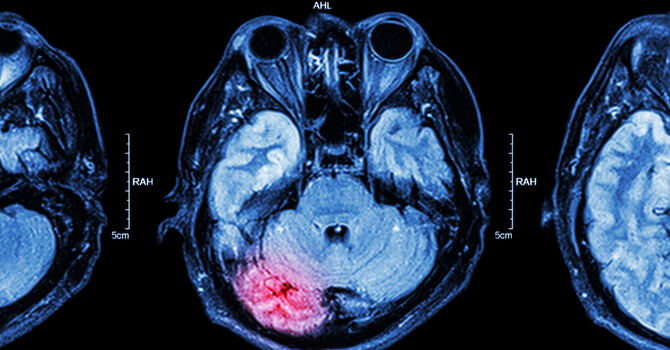

The Importance of Neuroimaging in Concussion Diagnosis and Recovery image

The Importance of Neuroimaging in Concussion Diagnosis and Recovery

Neuroimaging: A Powerful Tool for Red Flags, but Not the Full Story for Concussions When patients suffer a head...